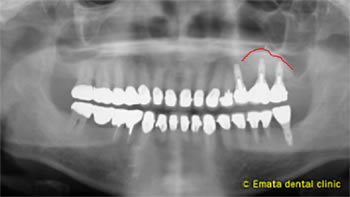

左上奥には骨がなく歯周病が原因で抜歯になったのでしょう

CT検査の結果、一部分が上顎洞と間に骨がないことががわかりました。上顎洞の炎症は見受けられません。